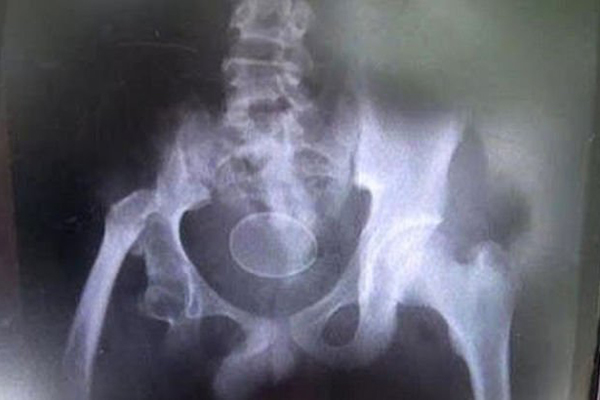

14 yaşındaki adı Akmal olarak açıklanan bir çocuk, doktorların önünde yumurtladı.Babasıyla birlikte bu nedenle hastaneye giden çocuk, son iki senede toplam 20 kere yumurtladığını iddia etti. 14 yaşındaki çocuk rahatsızlanması sonucu defalarca hastaneye kaldırılırken, doktorların önüne de 2 yumurta bıraktığı iddia edildi. Doktorlar, böyle bir olayın tıbben imkânsız olduğunu açıklayarak, yumurtaların çocuk rektumuna kasıtlı olarak sokulduğunu iddia etti. Ancak çocuk ve babası bu iddiaları yalanladı. Yerel basın da Akmal ve babasını destekleyen bir tutum sergilerken, doktorlar bunun üzerine olayı araştıracaklarını duyurdu.